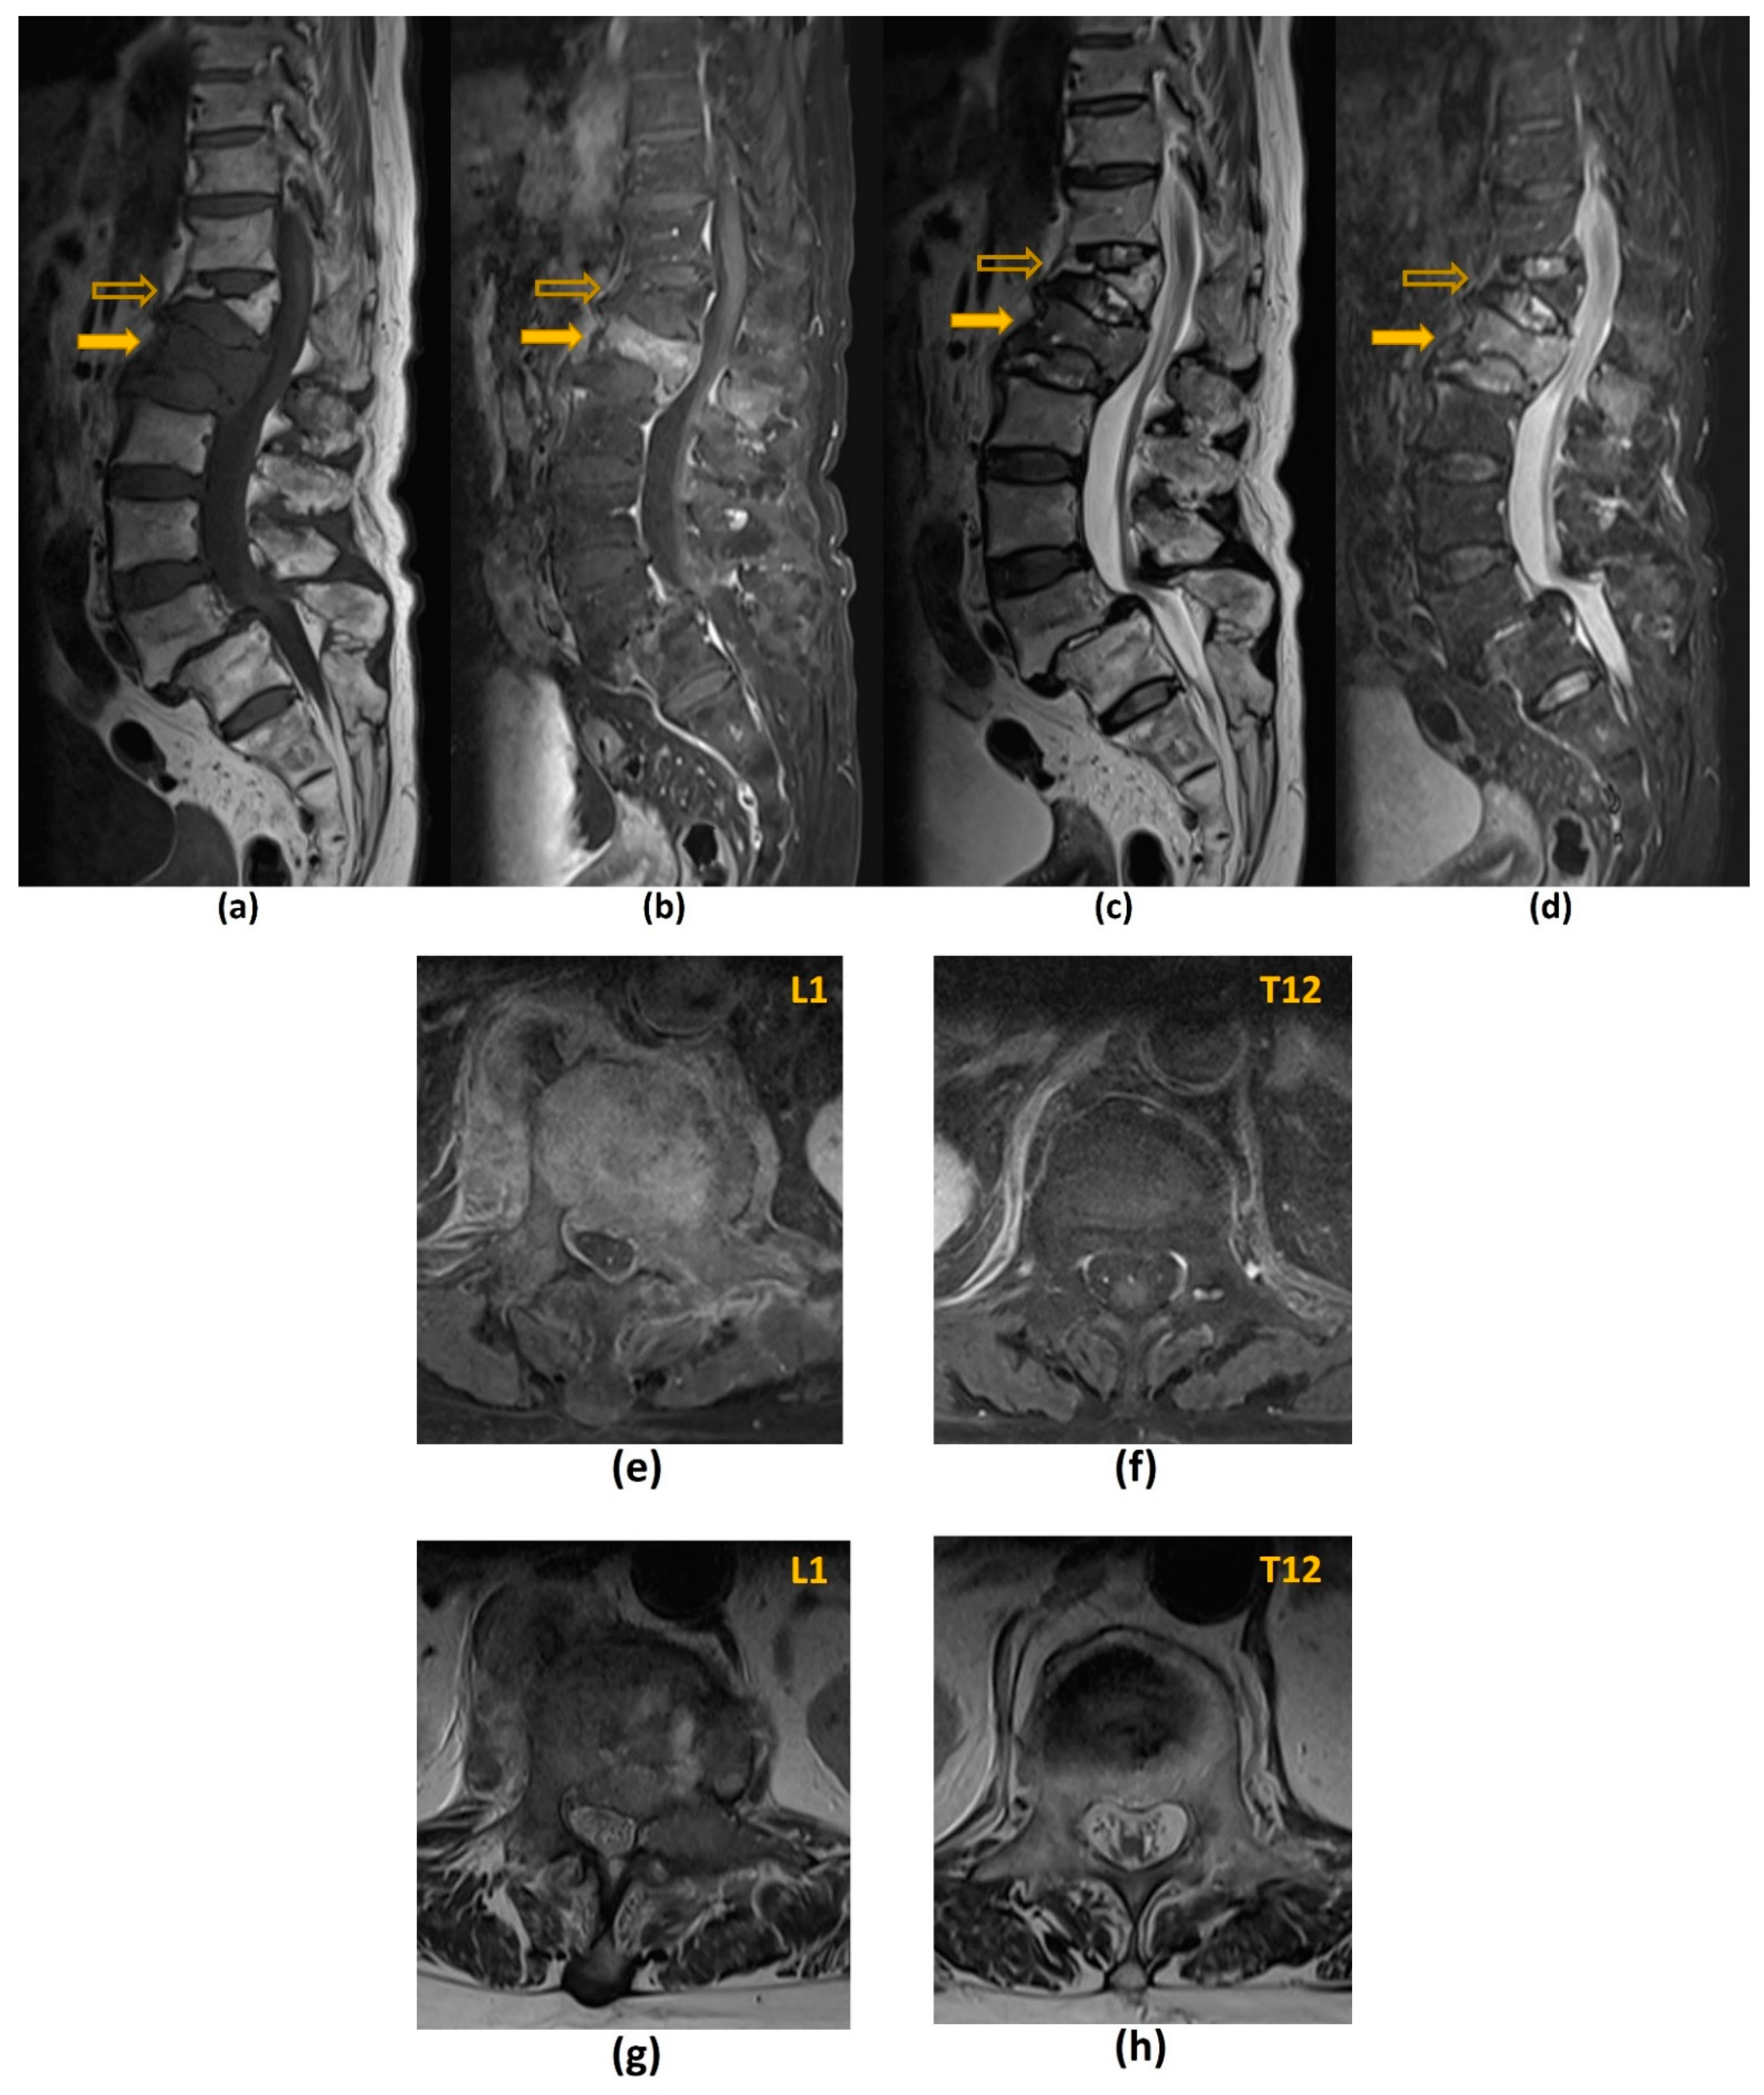

- Jung, H.S.; Jee, W.H.; McCauley, T.R.; Ha, K.Y.; Choi, K.H. Discrimination of metastatic from acute osteoporotic compression spinal fractures with MR imaging. Radiographics 2003, 23, 179–187. [Google Scholar] [CrossRef]

- Mauch, J.T.; Carr, C.M.; Cloft, H.; Diehn, F.E. Review of the Imaging Features of Benign Osteoporotic and Malignant Vertebral Compression Fractures. AJNR Am. J. Neuroradiol. 2018, 39, 1584–1592. [Google Scholar] [CrossRef]

- Arana, E.; Kovacs, F.M.; Royuela, A.; Asenjo, B.; Nagib, F.; Pérez-Aguilera, S.; Dejoz, M.; Cabrera-Zubizarreta, A.; García-Hidalgo, Y.; Estremera, A. Spanish Back Pain Research Network Task Force for the Improvement of Inter-Disciplinary Management of Spinal Metastasis. Metastatic Versus Osteoporotic Vertebral Fractures on MRI: A Blinded, Multicenter, and Multispecialty Observer Agreement Evaluation. J. Natl. Compr. Cancer Netw. 2020, 18, 267–273. [Google Scholar] [CrossRef] [Green Version]

| Benign Osteoporotic Compression Fracture | Malignant Vertebral Compression Fracture |

|---|---|

| Posterior retropulsion of bony fragments or a concave posterior border of the vertebral body | Expansile convex posterior cortex |

| Normal marrow signal intensity (or a well-demarcated regular margin separating the spared marrow and abnormal marrow within the fractured vertebra) | Reduced signal intensity on T1-weighted imaging reflecting an underlying marrow replacing process, particularly if the posterior elements are involved |

| Remains isointense post-contrast imaging | Heterogeneously increased enhancement of the vertebral body |

| Usually without involvement of the posterior vertebral elements | Involvement of the posterior elements |

| Presence of multiple compression fractures (with the notable exception of multiple myeloma) | Presence of other spinal metastasis |

| Presence of a T1-weighted and T2-weighted hypointense band (thought to represent cancellous bone compaction, fluid or gas-filled clefts) | Abnormal epidural or paraspinal soft tissue or enhancement |